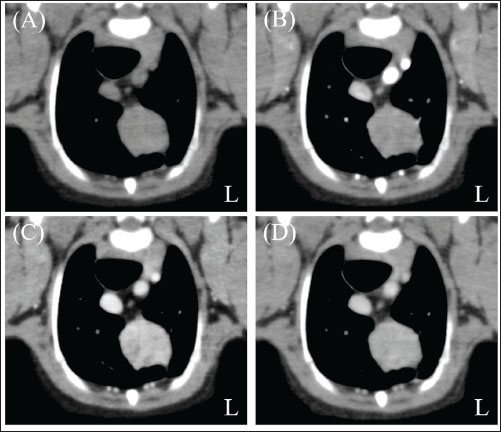

A neutered 9-year-old male Papillon weighing 3.5 kg was referred to the Okayama University of Science Veterinary Medical Teaching Hospital for examination and treatment of an incidentally discovered mass in the cranial intrathoracic cavity during regular medical checkups. The dog had no clinical signs and was in good general condition. However, a mass in the cranial thoracic region was detected by chest radiography. Blood tests showed no hypercalcemia, and arterial blood gas analysis showed no problems (Table 1). Polycythemia, slight hypernatremia, and hyperchloremia, which may be related to dehydration, were also observed. A chest X-ray revealed a mass of approximately 20 mm in the cranial intrathoracic cavity and mild expansion of the mediastinum (Fig. 1). The tumor-associated syndromes, such as megaesophagus and myasthenia gravis, were not observed. Computed tomography (CT) was performed under general anesthesia (Aquilion Lightning; Canon Medical Systems Co., Tokyo, Japan). Iopamidol (Oypalomin 300, Fuji Pharma, Japan) was used as a contrast medium (injection volume, 2.5 ml/kg [750 mgI/kg]; injection time, 15 seconds). Precontrast, arterial phase, venous phase, and equilibrium phase scans were obtained. The cranial intrathoracic mass (length, width, and height of 18.3, 16.0, and 18.6 mm, respectively) was a solitary lesion within the cranial mediastinum (Fig. 2). The mass was well demarcated, and there was no evidence of invasion into the surrounding blood vessels. The CT values of the mass were 43.2, 50.6, 113.1, and 102.2 HU for the precontrast, arterial, venous, and equilibrium phases, respectively (Fig. 2). These contrast enhancement effects were a preliminary diagnosis that the mass was a thymoma (Von Stade et al., 2019). Enlarged surrounding lymph nodes or distant metastasis were not detected. Due to the small size of the mass and its absence from the thoracic cavity margin, preoperative pathological examination could not be performed. Based on the CT results, the mass was provisionally diagnosed as a thymoma. The thymoma volume was measured from the length, width, and height by computed tomography using the elliptical volume formula. The cranial intrathoracic volume was measured using a 3D image analysis software (Ahmics-VAZE, PetCommunications Co., Ltd., Osaka, Japan). The cranial intrathoracic region between the first and fourth sternum at the beginning of the cranial intrathoracic cavity was assumed to be the surgical space for VATS-T (Fig. 3). The dorsal cephalic end was designated as the point where the first sternum extends perpendicularly and joins the thoracic vertebrae, and the dorsal caudal end was designated as the point where the fourth sternum extends perpendicularly and joins the thoracic vertebrae. This region was extracted and its volume was measured using the 3D volume rendering function by Ahmics-VAZE. The ratio of thymoma volume to cranial intrathoracic volume (T/CI ratio) was calculated as follows: thymoma volume/cranial intrathoracic volume × 100). The thymoma volume was 2.3 cm3, the cranial intrathoracic volume was 97.7 cm3, and the T/CI ratio was 2.4%. The thymoma volume was calculated using the approach in a previous report of two cases that described the thoracoscopic resection of thymomas (Mayhew and Friedberg, 2008). We also calculated the cranial intrathoracic volume for the dog, as it was of the same breed and weight as the two reported cases. Subsequently, we calculated the T/CI ratio. In previous reports, the thymoma volumes were 9.5 cm3 and 36.6 cm3, respectively, and the cranial intrathoracic volume was 892.8 cm3. The T/CI ratios were 1.1% and 4.1%, respectively.

Fig. 2. Chest computed tomography (CT) imaging. (A) Pre-contrast phase. (B) Arterial phase. (C) Venous phase. (D) The equilibrium phase. The cranial chest mass (length, width, and height of 18.3, 16.0, and 18.6 mm, respectively) was a solitary lesion within the cranial mediastinum. The lesion was well demarcated and showed no signs of invasion into the surrounding blood vessels. The CT values of the lesion were 43.2 HU for the pre-contrast phase (A), 50.6 HU for the arterial phase (B), 113.1 HU for the venous phase (C), and 102.2 HU for the equilibrium phase (D) (L): Left side.